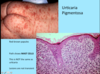

A: Describe Histology (3)

B: Dz

C: Location (2)

D: What’s this Dz caveat

A: image

B: Acanthosis Nigricans

C: Axilla and Neck Creases

D: THERE IS NO ACANTHOSIS ON HISTOLOGY

A: Describe Histology (3)

B: Dz

C: Location (2)

D: What’s this Dz caveat

A: image

B: Acanthosis Nigricans

C: Axilla and Neck Creases

D: THERE IS NO ACANTHOSIS ON HISTOLOGY